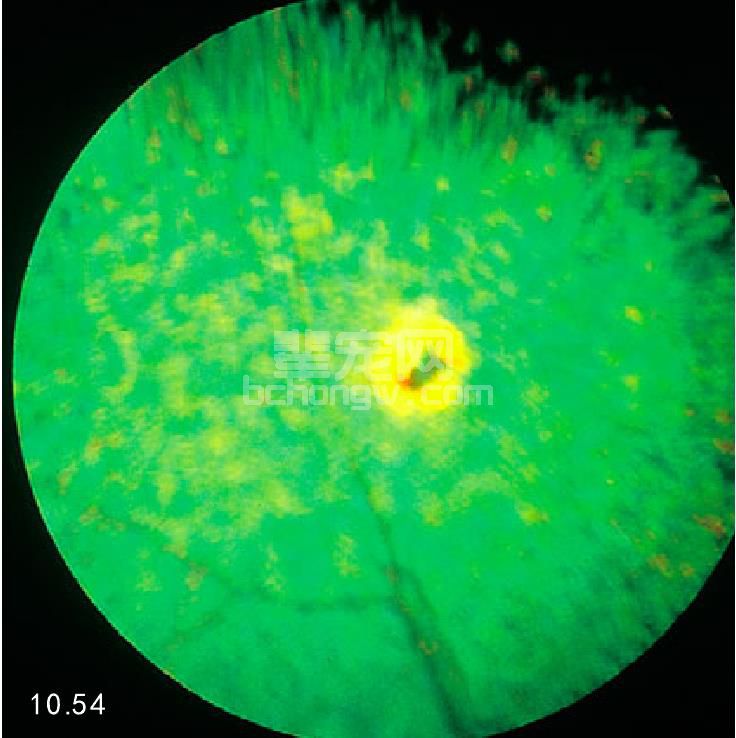

临床症状 视网膜或脉络膜视网膜炎症的症状包括:水肿、炎性细胞浸润和形成肉芽肿、出血及存在渗出性 视网膜脱落的可能(图10.52和图10.53)。犬视网膜渗出、出血、脱落是本病的后续症状(图10.54)。

图10.54 猫的非活动性脉络膜视网膜炎,导致视 网膜萎缩而呈现过度反光区。